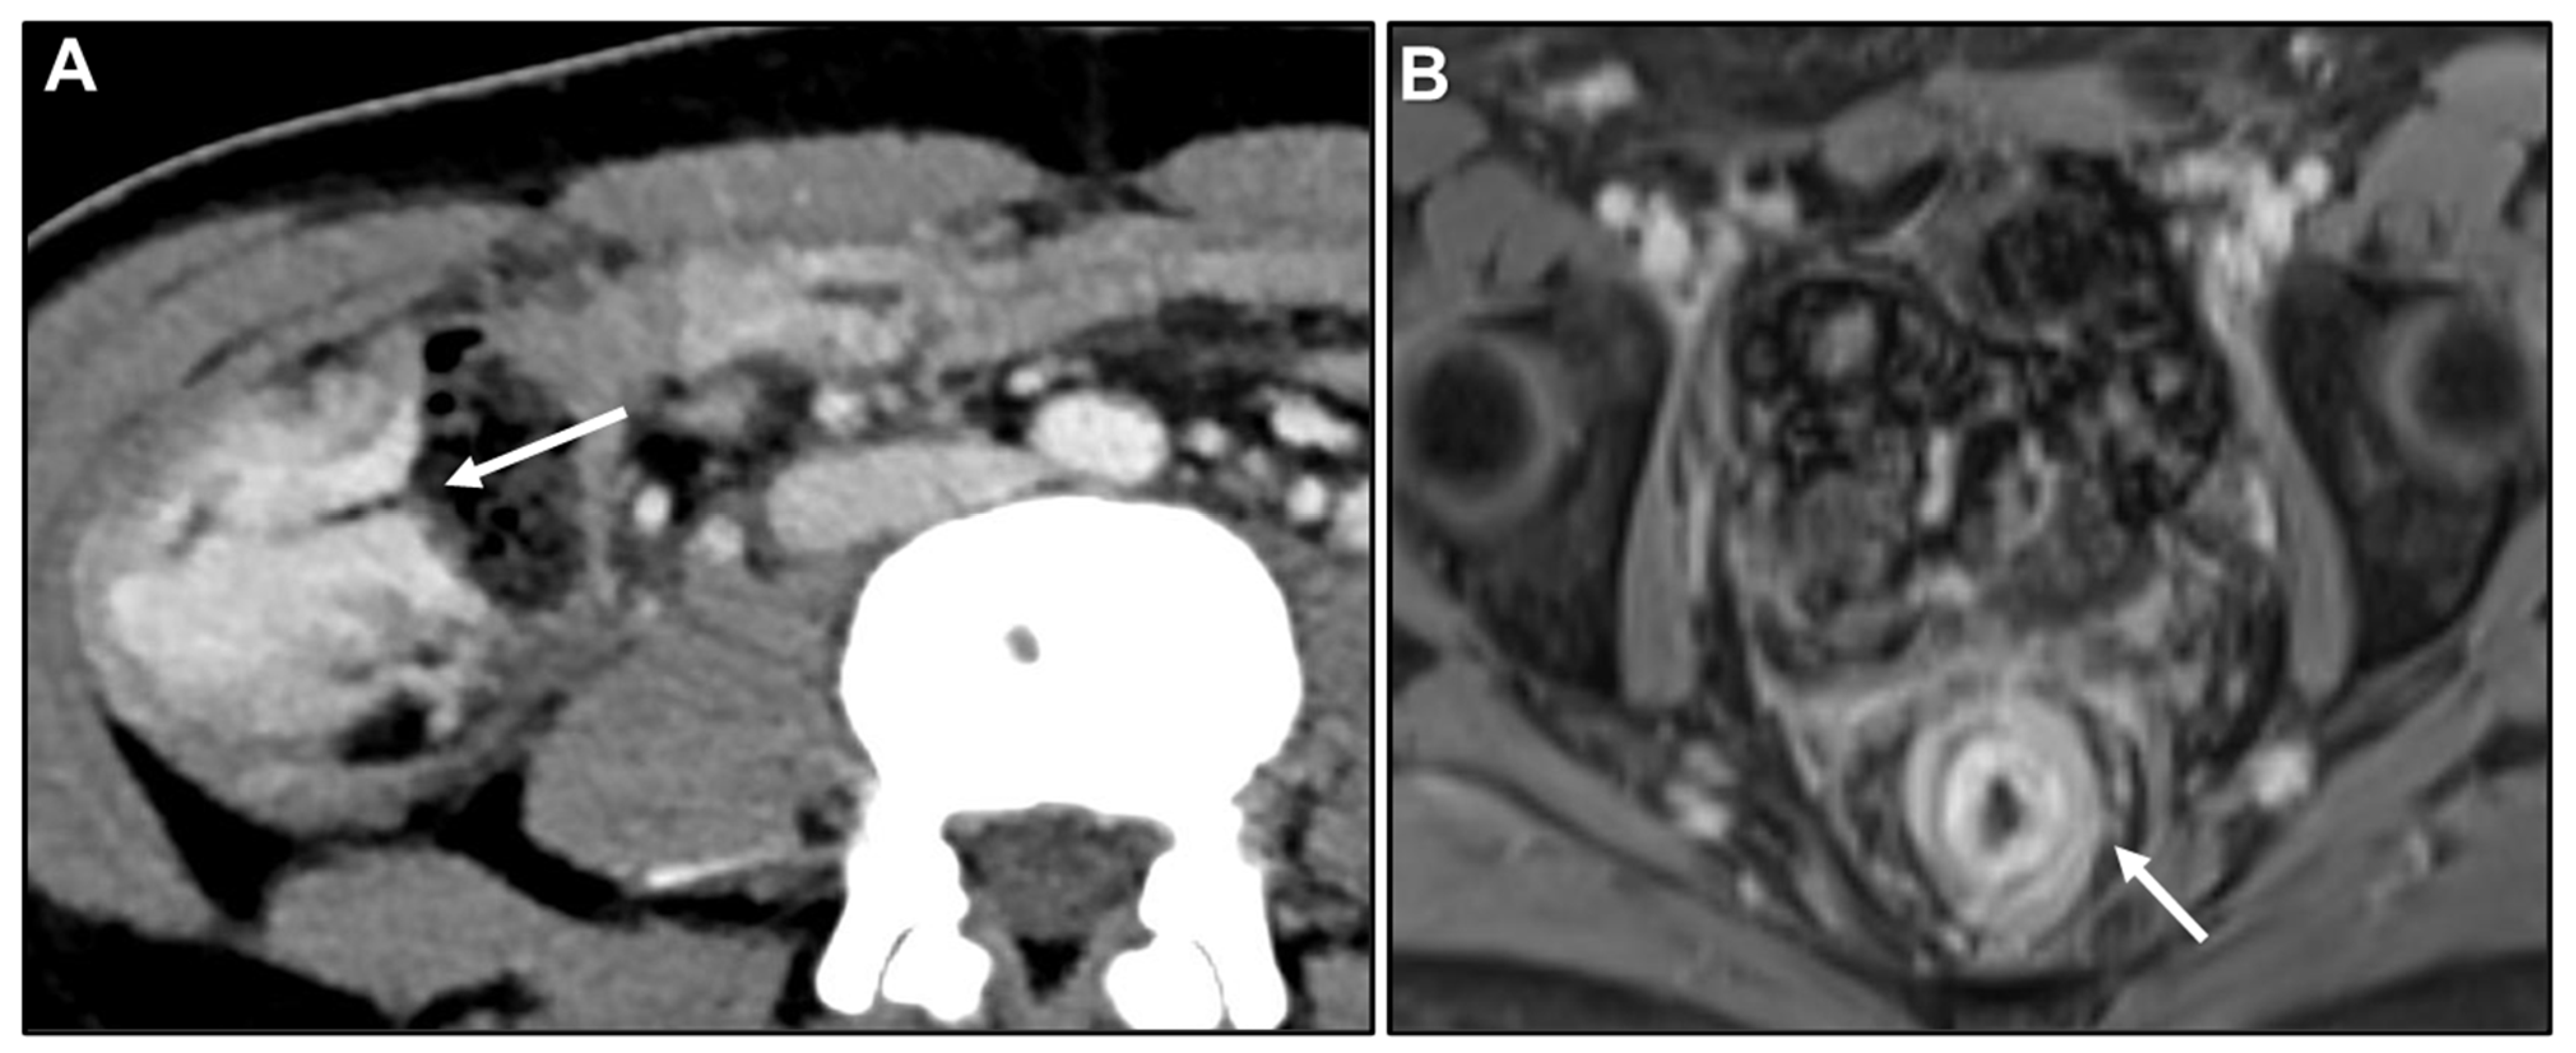

Peritoneal Carcinomatosis

Presacral Fat Tissue and Rectovaginal Septum Infiltration and T2-Weighted Imaging (T2WI) Hypointense Extramural Tumour Component